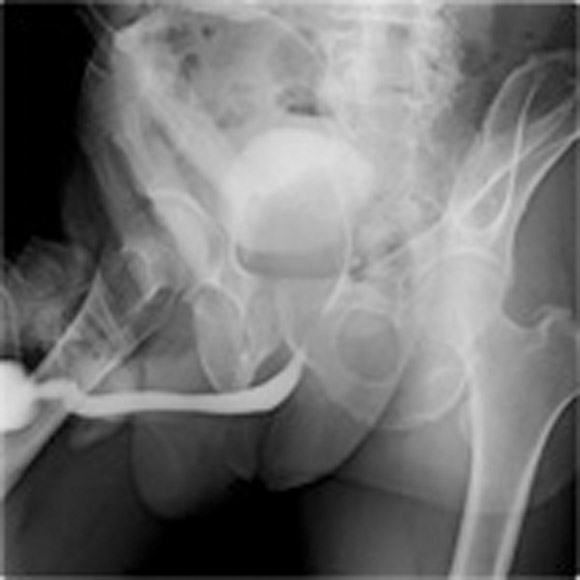

X線透視下にて尿道口より逆行性に造影剤を注入しながら撮影します。 尿道・膀胱・前立腺の形態が分かるため、尿道狭窄や前立腺肥大の診断に用いる検査です。